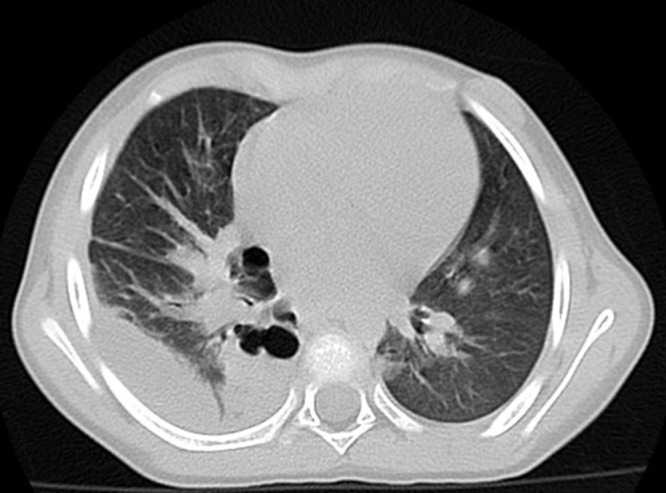

Methods: This case report presents the case of a 4 years and 5 months old patient diagnosed with invasive pneumococcal-associated pneumococcal infection in the context of SARS-COV2 infection.

Abstract Image